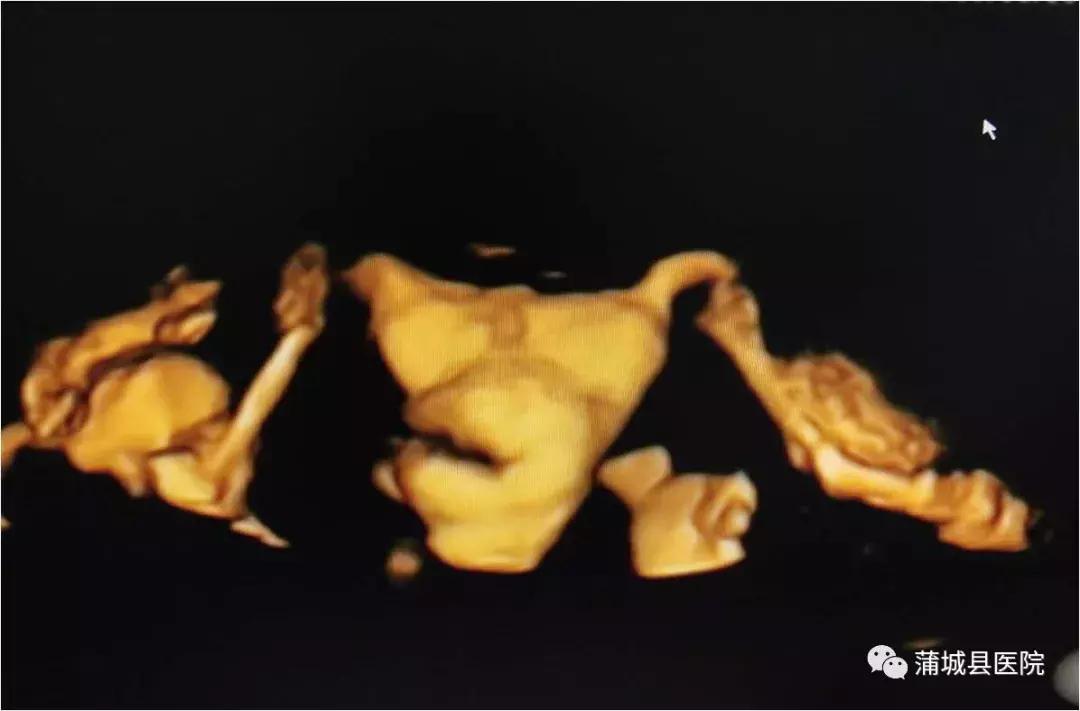

蒲城县医院超声科引进的 美国GEVolusonE8彩色多普勒超声仪和超声造影剂六氟化硫微泡(声诺维),可以用于三维/四维子宫输卵管超声造影检查。超声输卵管造影术是通过向宫腔注入造影剂后,使原本闭合的宫腔和输卵管扩张,然后进行三维成像,主要用于评价输卵管通畅性和诊断子宫宫腔病变。由于子宫输卵管超声造影和三维超声的完美结合,超声声像图的质量得到明显改善,并可获得更多的信息,使诊断的敏感性和特异性显著提高。

三维/四维超声输卵管造影,能够快速、准确地评估输卵管的通畅性,是筛查输卵管通畅性的有效手段。